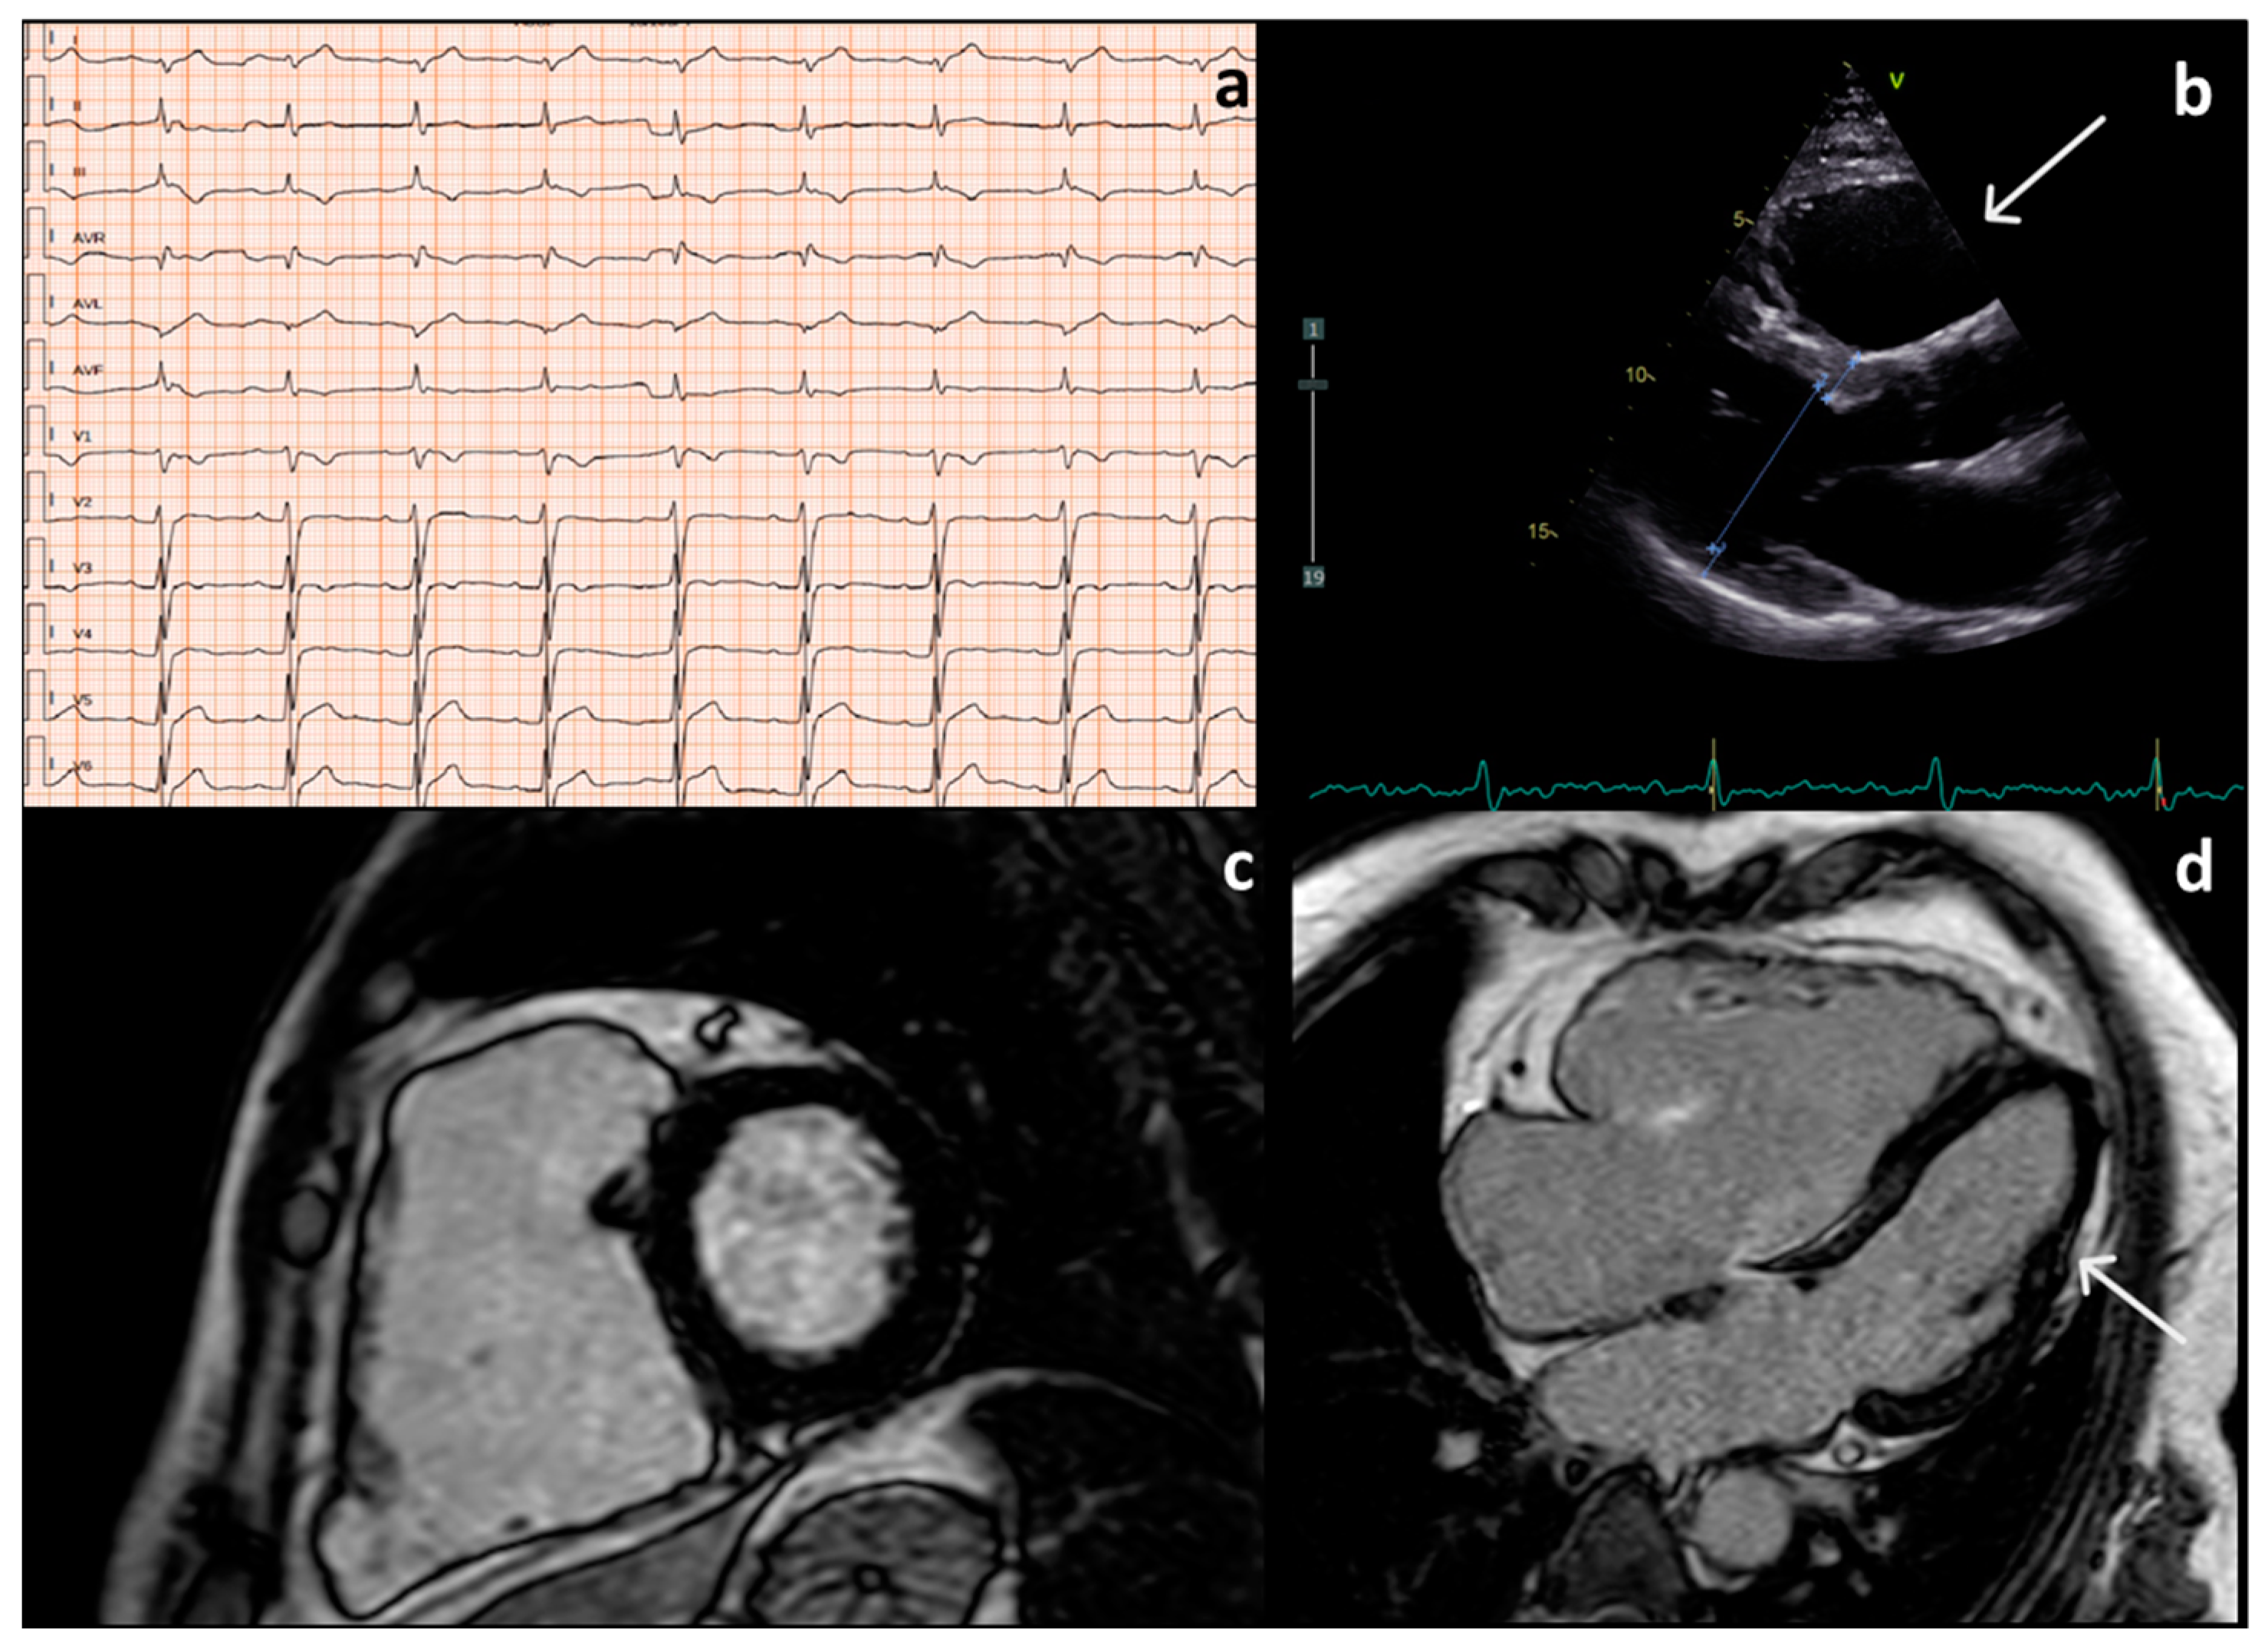

- Repolarization Abnormalities (inverted T waves in right precordial leads);

- Depolarization/Conduction Abnormalities (ε waves in the right precordial leads, prolonged QRS duration);

| Fam; pt | Sex | Symptoms | ECG Findings | Morphofunctional Abnormalities | ||||||||

|---|---|---|---|---|---|---|---|---|---|---|---|---|

| Palpitations | Syncope | Low QRS | ε-Waves | Negative | Negative | RV | RV | RV | LV | LGE | ||

| Voltage | T Waves in Leads | T Waves Beyond Lead V3 | Dilation | Dysfunction | Regional | Dilation | ||||||

| in Limb Leads | V1-V2/V3 | WMA | ||||||||||

| Fam 2; III:3 | F | yes | / | / | yes | yes | yes | yes | yes | bulging | / | no |

| Fam 2; III:1 | F | yes | yes | / | / | yes | yes | / | yes | bulging | / | yes |

| Fam 1; II:2 | M | yes | / | yes | yes | / | / | yes | yes | bulging | yes | no |